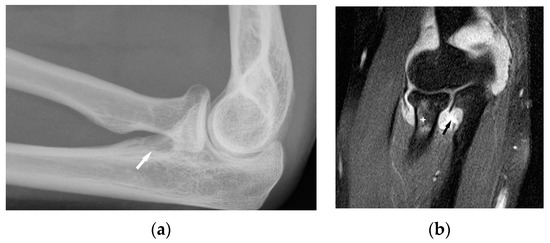

Figure 5. Radiograph (a) and MRI of the elbow (b) performed in a 45-year-old woman with sarcoidosis. Osteolytic lesion in the proximal part of the elbow bone ((a), white arrow). T2-weighted image with fat saturation revealed a synovitis, erosion in the proximal part of the elbow bone corresponding to this bone lesion (black arrow) and slight bone marrow edema in the head and neck of the radius (asterisk).

Chronic arthritis, either mono-articular or poly-articular, occurs in the later phases of the disease, usually as a part of a multisystem manifestation. In addition to synovitis (Figure 5a,b), erosions of the articular surfaces may be present, making it necessary to differentiate the lesions from reactive or rheumatoid arthritis [19]. An additional difficulty is that the rheumatoid factor may be positive in 10–47% of cases [20]. If differential diagnosis is necessary, a synovial US-guided biopsy is performed. Detection of granulomas in a synovial biopsy sample helps make the diagnosis of sarcoidosis [20]. X-ray shows soft tissue swelling and epiphyseal demineralization.

Long-lasting joint inflammation leads to the narrowing of the joint space. In the sarcoid arthritis diagnostic imaging, we mainly use X-ray, US, and MR imaging. MRI shows with high sensitivity the joint effusion and features of synovitis, cartilage destruction, and inflammatory changes of periarticular structures such as peritendinitis, tendinitis or bursitis (Figure 5a,b) [20].